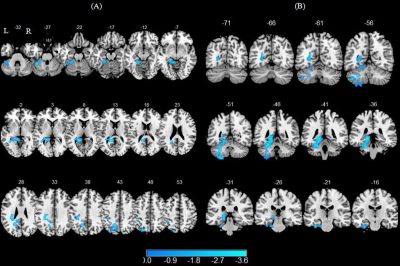

In comparison of nonsmokers, smokers showed increased ALFF in left superior frontal gyrus (SFG), medial superior frontal gyrus (mSFG) and middle frontal gyrus (MFG) as well as decreased ALFF in right calcarine sulcus (GRF corrected P < 0.005) (Figure 1).

In comparison of nonsmokers, smokers showed attenuated functional connectivity with left SFG in left precuneus, fusiform, lingual gyrus, cerebellum 4 5 and cerebellum 6 as well as lower functional connectivity with left mSGF in left fusiform, lingual, parahippocampal gyrus (PHG), calcarine sulcus, cerebellum 4 5, cerebellum 6 and cerebellum 8 (GRF corrected P < 0.005) (Figure 2).

Figure 1: Smokers showed significant differences in ALFF. Regions of increased ALFF were shown in red and decreased ALFF were shown in blue.

Figure 2: Altered resting-state functional connectivity with the left superior frontal gyrus (SFG) and left medial superior frontal gyrus (mSFG). Brain regions with decreased functional connectivity to the left SFG are shown in panel (A). Brain regions with decreased functional connectivity to the left mSFG are shown in panel (B).